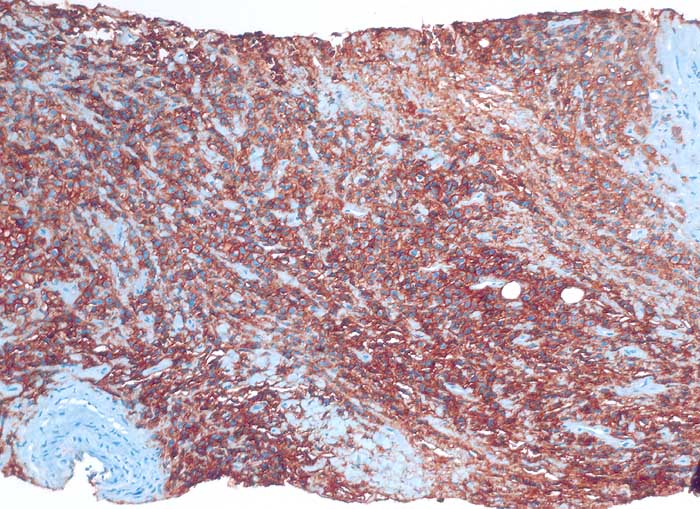

Diffuse grosszellige B-Zell Lymphome treten nicht selten in extranodalen Lokalisationen auf und können klinisch als Karzinom fehlgedeutet werden. Bei ungewöhnlicher Zytomorphologie eines malignen Tumors sollte deshalb immer auch an die Möglichkeit eines nicht epithelialen Tumors gedacht und der Befund mittels Immunzytochemie weiter abgeklärt werden. Zur Unterscheidung eines Lymphoms von einem epithelialen Tumor eignen sich der panleukozytäre Marker CD45 (LCA) und ein Panzytokeratinmarker oder BerEP4.

Beim ersten Fall handelt es sich um ein primär extranodales Lymphom des Nierenbeckens, das im Urin diagnostiziert wurde. Beim zweiten Fall handelt es sich um ein primär extranodales Lymphom im Bereich der Nebenniere mit Nachweis von Lymphomzellen im Aszites.